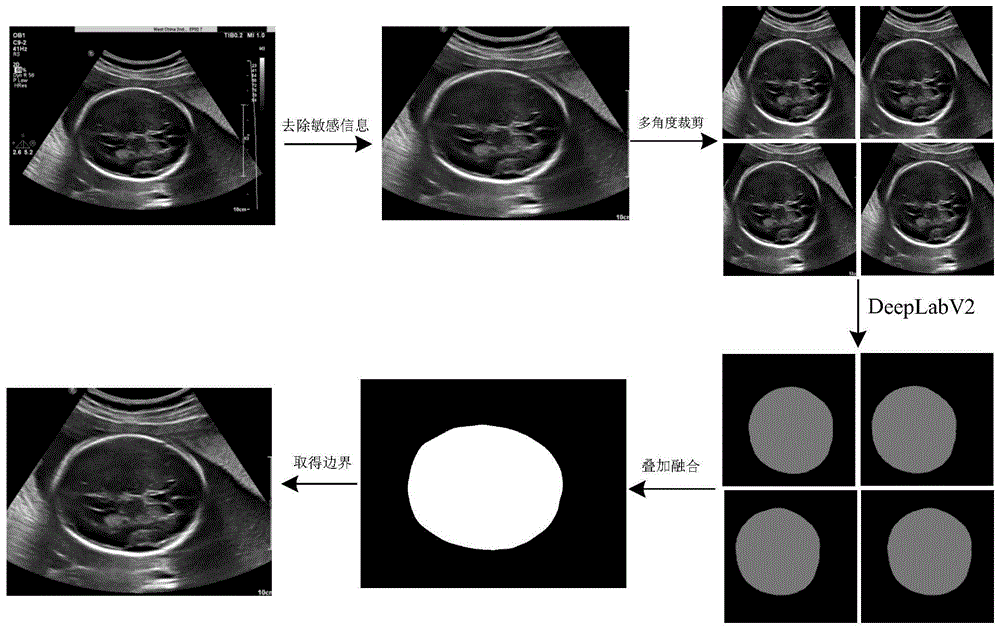

一种基于卷积神经网络的胎儿头围自动精确测量方法